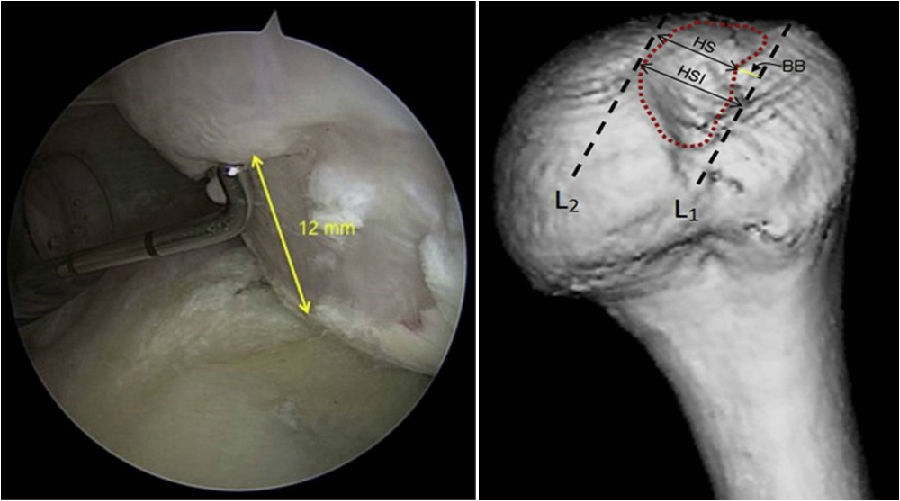

四、肩关节脱位轨迹评估:关节镜下测量评估法

关节镜下肩胛盂轨迹(Glenoid Track,GT)评估是金标准,可以监测一侧骨缺损、Hill-sachs损伤间距评估。

术中通过评估肩胛盂轨迹,可以计算出骨缺损的范围和比例,另外评测肱骨头凹陷区域距离。

图31 D:15X2=30mm,d:15-10=5mm,83%D=24.9mm,d/D=16.7%

根据公式,可以计算出存在骨缺损的肩胛盂轨迹(0.83D-d),此例中的肩胛盂轨迹为0.83×30-5=19.9mm。

图32 Hill-Sachs损伤测量方式

上图为Hill-Sachs损伤的测量方式,采用前端为4mm的探钩,可以看到Hill-Sachs损伤的区域为3个探钩前端的跨度,因此HS为12mm。

评估报告提示:肩胛盂轨迹(Glenoid Track,GT)19.9mm,Hill-Sachs间距(Hill-Sachs Interval,HSI)24mm。

图34 BB=12

骨桥宽度的测量方式,采用前端为4mm宽的探钩测量,发现骨桥宽度正好为3个探钩前端的跨度,应为12mm。

计算Hill-Sachs间距(Hill-Sachs Interval,HIS)。这个间距应为Hill-Sachs损伤的宽度(HS)加上骨桥(Hill-Sachs损伤的外侧缘到肩袖止点)的宽度(BB),HSI:HS+BB=24mm。